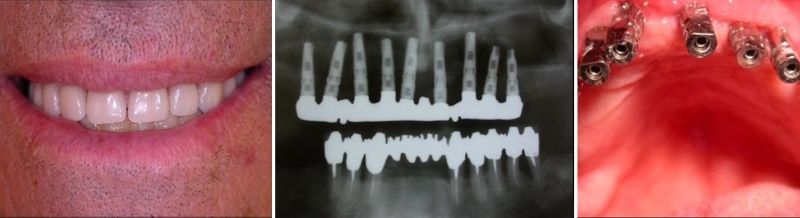

מקרה 2:

שיקום אסתטי של שיניים קידמיות על ידי שתלים - לפני

שיקום אסתטי של שיניים קידמיות על ידי שתלים - אחרי